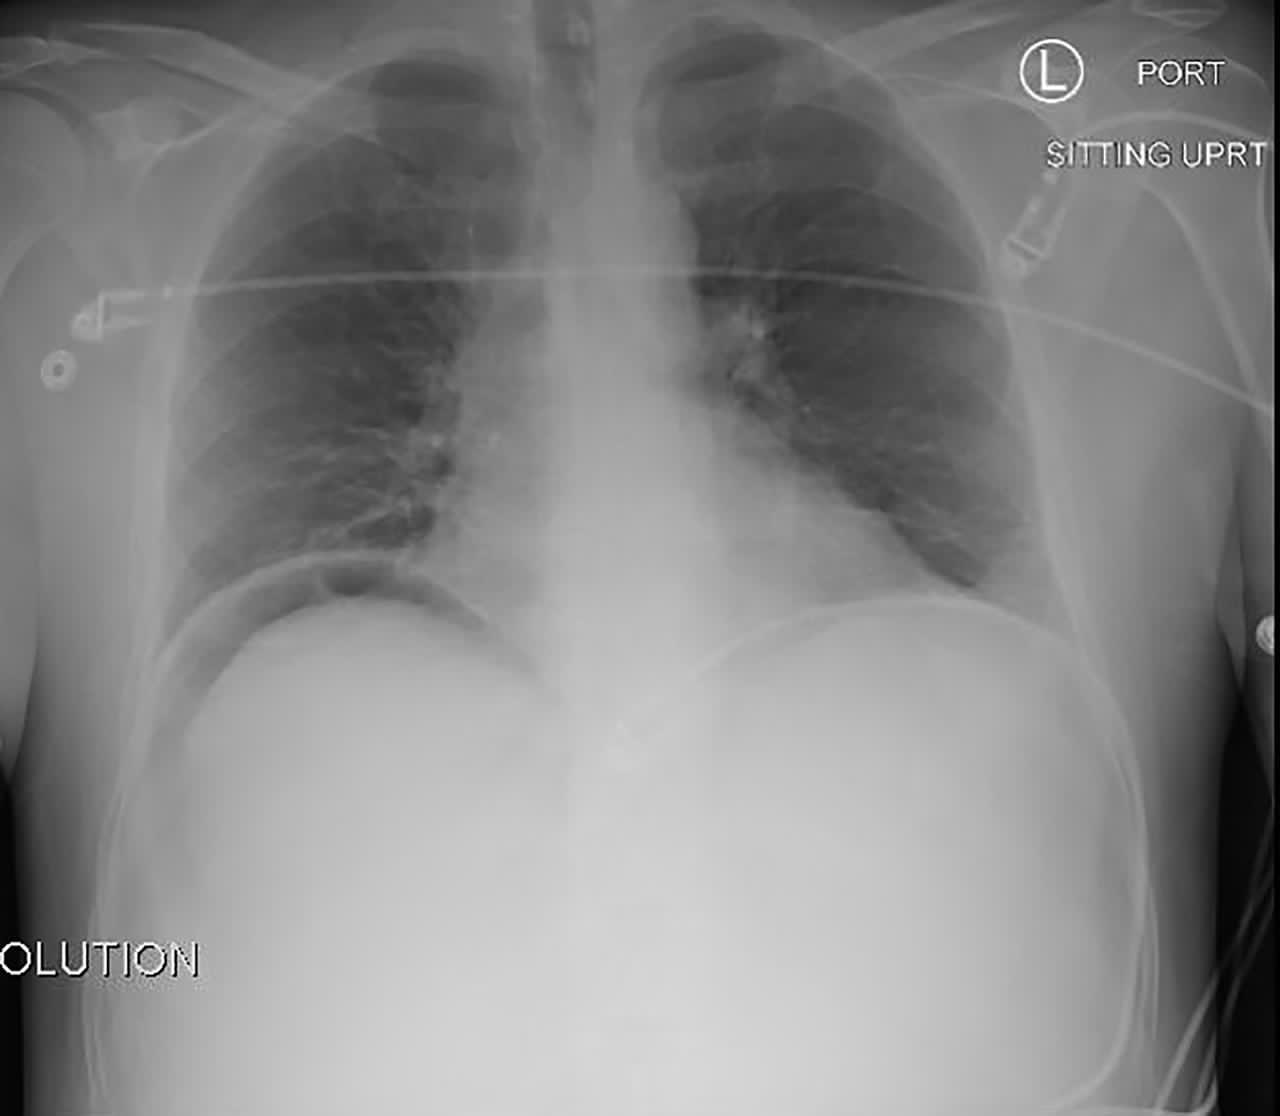

وتفصيلاً، استقبل قسم الإسعاف والطوارئ، حالة لمواطن في العقد الثامن من العمر، كان يعاني من الام حادة بالبطن، وبعد إجراء التحاليل والفحوصات اللازمة، تبين انه يعاني من ثقب في الأمعاء نتج عنه التهاب شديد في الغشاء البريتوني أدي لدخول المريض بصدمة تسممية.

وعلى الفور، تم توجيه المريض لغرفة العمليات وشرح الحالة لاستشاري التخدير الدكتور محمد شعبان واخصائي التخدير محمد أبو علي، كون المريض طاعن في السن، ويعاني من مرض السكر وأرتفاع ضغط الدم مع ضعف في وظائف بعضله القلب والرئتين؛ وبحاجة عاجلة لإجراء عملية استكشاف، حيث نجح فريق التخدير من تنويمه طوال فترة العملية والتي استغرقت أكثر من 3 ساعات “.

وبفضل من الله- تمكن فريق الطبي بقيادة استشاري الجراحة العامة الدكتور هشام بركات والدكتور محمد العقباوي اخصائي الجراحة العامة، من إجراء العملية، التي تبين من خلالها وجود ثقب في الأمعاء (الاثني عشر) مع وجود التهاب شديد بالبطن والتصاقات بالأمعاء، حيث تم إصلاح الثقب وتنظيف البطن-حيث تكللت بالنجاح، فيما ظل المريض تحت المتابعة لأكثر من عشرة أيام حتى تحسن وخرج لمنزله وهو بصحة جيدة”.